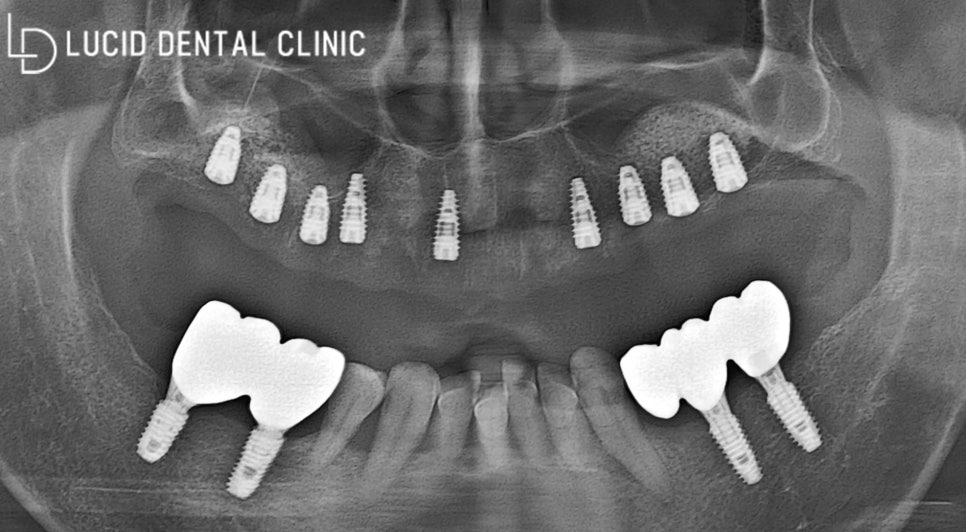

따라서 언주역 치과 는 환자의 요구대로

전체 임플란트 시술 을 진행하되,

픽스처를 제대로 고정할 골이 부족하니

상악동 골 이식술을 시행하기로 했습니다.

먼저 간단하게 스케일링을 시행하여

혹시 모를 이차 감염을 예방하고,

환자께서 통증을 덜 느끼도록

마취를 놓아드렸습니다.

우선 이 전에 심어져 있던

픽스처부터 제거했는데요.

기존 보철을 제거하자마자

새로운 픽스처를 식립하기 위해

상악동 골 이식을 진행하였습니다.

그 후, 상악동을 들어 올려

골 이식을 충분히 진행하고

제작한 가이드를 이용하여

즉시 식립을 마쳤습니다.

현재 환자께선 아직 회복 중이라

보철을 올리지 않은 상태인데요.